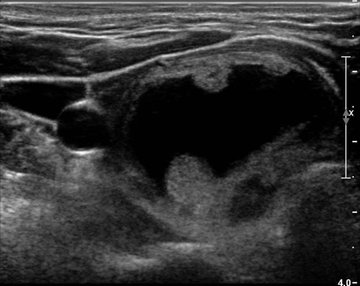

Sometimes your doctor detects a thyroid nodule when you have an imaging test. Web The ACR TI-RADS Thyroid Imaging Reporting and Data System is a 5-point scoring system for thyroid nodules based on ultrasound findings developed by the American. A thyroid fine needle aspiration biopsy can collect samples of cells from the nodule which.

Web Ultrasound can help evaluate a thyroid nodule and determine the need for biopsy. The One Thing You Should Be Eating for Your Thyroid Every Morning. Web Fleischner Society pulmonary nodule recommendation calculator volume-based 2017 version Volume doubling time.